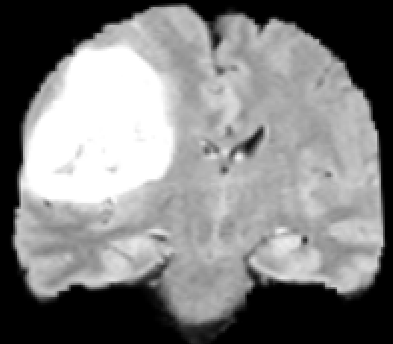

Refer to caption

Figure 1: MRI of a brain with a tumor from different angles